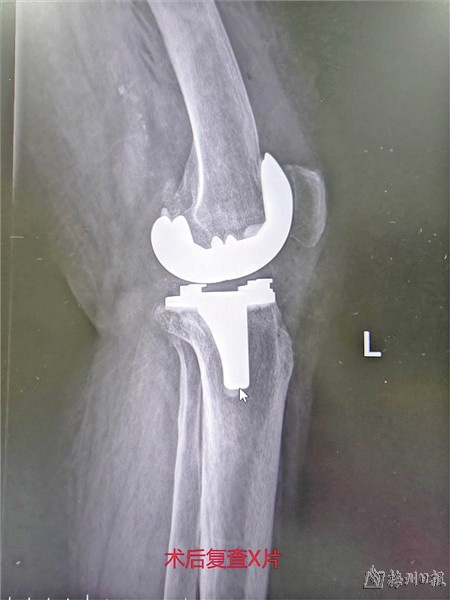

经过陈浩明主任团队的默契合作,手术十分顺利地完成。术后患者复查X光片显示:膝关节假体位置合理,左膝关节畸形得到充分纠正。术后第二天,丘奶奶已经可以在助行器的帮助下下地行走,随后顺利出院。